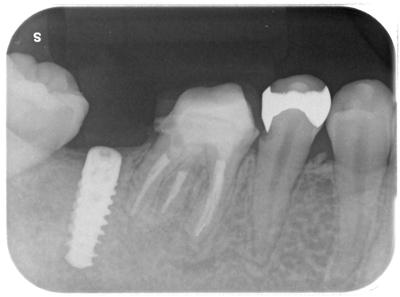

7┓部へのITI-BLXインプラントによる治療。

この部位へのインプラント治療には様々な治療設計、議論はあると思うが、他の歯牙の状況、全顎的矯正治療を行っている事、その他患者さんの要望からこのような治療計画となった。

7┓は虫歯が深く、大きく膿が溜まっており保存不可能。

6┓も根尖に影=膿が溜まっている、しかも前医によるファイル破折が起きているが、何の説明もなかったとのこと。

虫歯も深い。

7┓抜歯後、インプラント埋入直後(待機埋入)

6┓は根管治療行ったが、マイクロスコープ下でも破折ファイル片の除去はできなかった。無理して除去続行し、歯をダメにしては元も子もないので、徹底的に根管洗浄、一部MTAによる根管充填行った結果、根尖病巣は縮小、消失した。

深い虫歯には歯周外科処置を行っている。